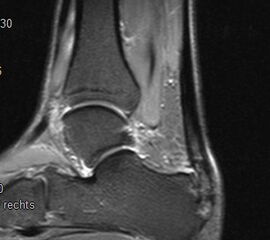

Abbildung 6: Darstellung des Baxter Nerven im MRT (siehe Pfeil)

Zum Lesen der Bildbeschreibung und zur Vollansicht bitte das Bild anklicken. Bild: Manfred Thomas.